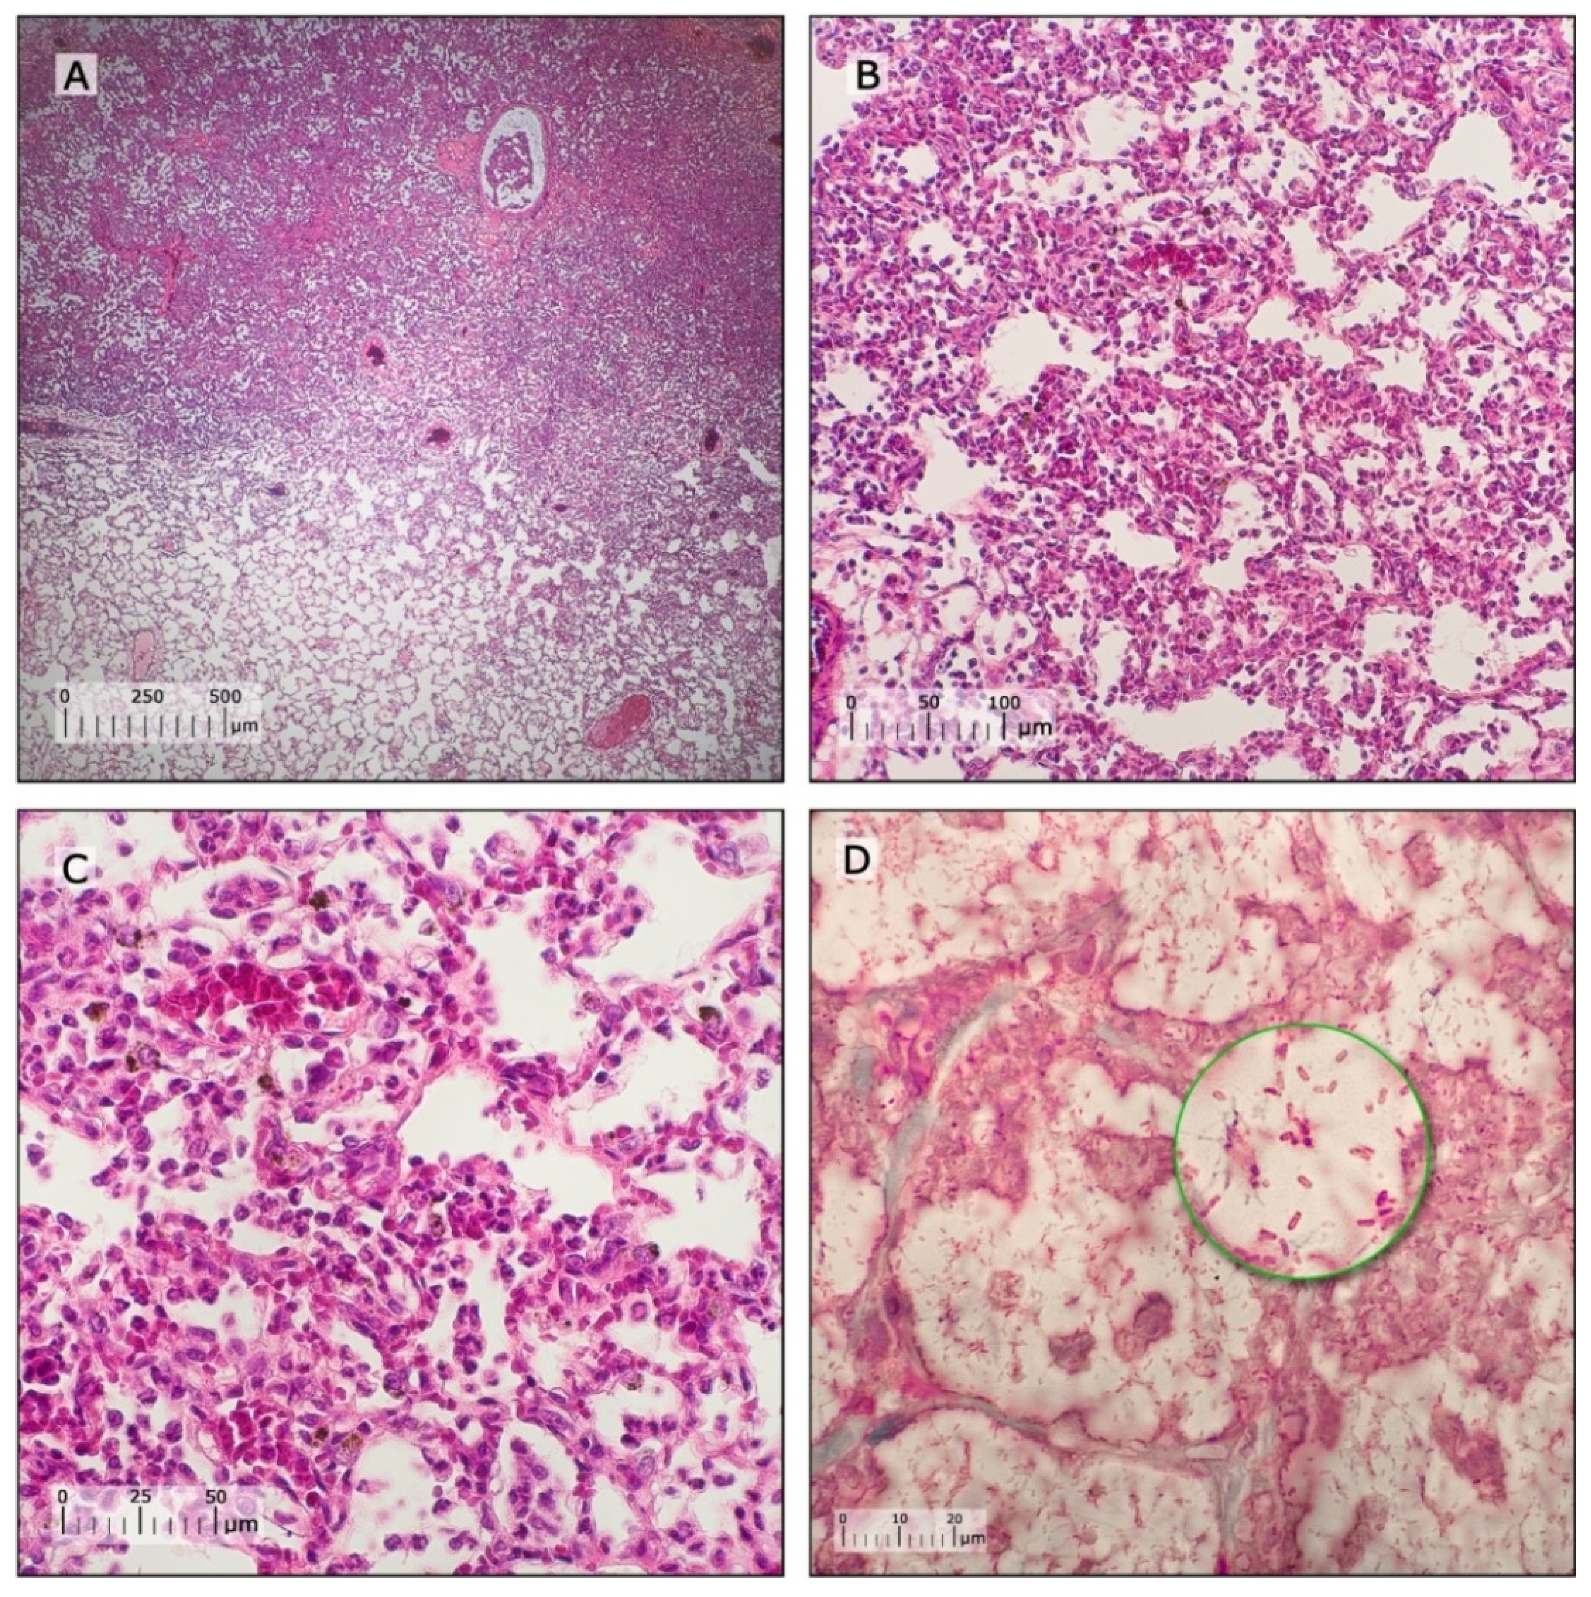

3.4. Characterization of Pneumonia–Septicemia Model